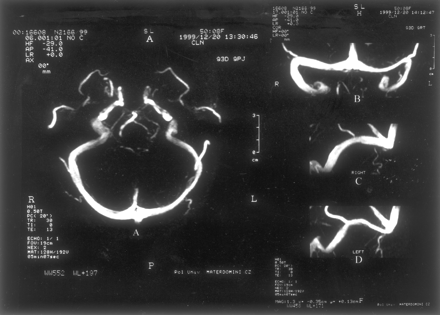

我们调查了111例正常脑脊液压力188金宝慱官网下载(60 - 192毫米范围H2O;意思是135;SD 33)。所有受试者正常的大脑直接上级矢状先生和鼻窦,盖伦的静脉,和内部脑静脉被认为在所有情况下,而枕窦是只有5%的病人。MRV显示正确,左,或共显性的TS在51%,18%,31%的病例。六十六例正常MRV (图1)而45主题显示干扰的一个或两个TS流。流的扰动分类为流动间隙如果缺乏信号流的长度小于或等于三分之一窦。在一个TS流差距观察静脉造影照片先生在29.7% (33/111);188金宝慱官网下载其中,36.4%(12/33)发生在占主导地位的TS。剩下的21例焦流缺口被认为在非惯用(42.4%,14/33)TS的窦或被认为是共显性的(21.2%,7/33)。流缺口位于近端部分TS在15%(5/33)的被试(图2),而流量差距mid-lateral部分TS中85%(28/33)的人(图3)。关于后个人,其中75%(21/28)有焦空白暗示蛛网膜颗粒的流动。缺乏信号流在一个整个TS在9%(10/111)的病例。188金宝慱官网下载值得注意的是,只有2个人(1.8%)焦TS流缺口。

值得注意的是流差距主要被发现在TS的mid-lateral部分85%的个体,而只有15%的情况下显示的近端部分TS流差距。因为蛛网膜颗粒通常发生在TS的mid-lateral部分,可以假设在某些个人突出蛛网膜颗粒(或血栓形成在这些解剖结构)可能产生相对腔妥协从而导致压力梯度或扰流。同意这个结果,一些作者10显示硬脑膜的鼻窦的小型或大型蛛网膜颗粒19 29尸体标本;这些发现的绝大多数在TS左侧优势和优惠的本地化mid-lateral窦的一部分。同意这个结果,增强对比度MRV或对比增强CT脑鼻窦的研究显示蛛网膜颗粒的发生在13%和24%的主题。10不同于差距发生在mid-lateral部分TS流,流缺口位于鼻窦的近端部分可能是由于近端发育不全的TS。最后,10 111例(9%)受试者缺乏流信号在整个TS。整个TS的发育不全可能解释这一发现。188金宝慱官网下载